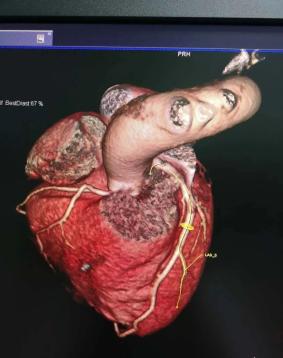

鄂托克前旗人民医院放射科最新引进西门子64排128层螺旋CT,于4月22日开展了首例冠脉CTA检查。64排128层螺旋CT与16排、32排CT相比,可以让临床医生看到更多更为精确的细节,其层厚更薄,扫描时间更短,辐射剂量更少,图像更清晰,功能更强大。可提高冠心病,脑血管疾病,各种肿瘤等诊断准确率,同时有利于各种疾病的预后评估与早期筛查。

成像软件方面有了更完善的改进,采集的数据既可做常规图像显示,也可在工作站进行后处理,完成三维立体重建、多层面重建、器官表面重建等,并能实时或近于实时显示,通过调节重建阈值,可逐层显示软组织和骨性结构,尤其适用于头颅、颌面部、脊柱、骨关节等部位三维结构的显示,可获得更加精细的三维立体图像。另外,由于VCT分辨力的各向同性,在得到常规断面图像结果同时,获得近似于内窥镜检查的管腔内部结构信息,适用于副鼻窦、气管支气管、胃肠道及血管等管腔结构的显示,可以不同角度的旋转、不同颜色的标记,使图像更具立体感、更直观、逼真。

其独具的无创、高效、精确、立体的医学影像技术,在检查状动脉有无狭窄、搭桥、支架的形态学以及心功能分析上有较强的优越性。实现了冠状动脉的无创检查,有着显影快、图像清晰的独特优势,并解决了心率及容积效应等主要影响图像质量的因素,为冠心病的筛选普查及诊断提供了一种安全、迅速、费用低廉的检查方法。此外,64排螺旋CT不但可以进行形态学的诊断,还可以用于功能成像诊断,如脑灌注成像的应用等,可以早期显示脑缺血灶。因扫描速度快,64排螺旋CT在急诊医学及早期肺栓塞的诊断上有独特优势,还可用于筛选冠心病、肺癌、肝硬化等,并进行良性与恶性肿瘤的分析。